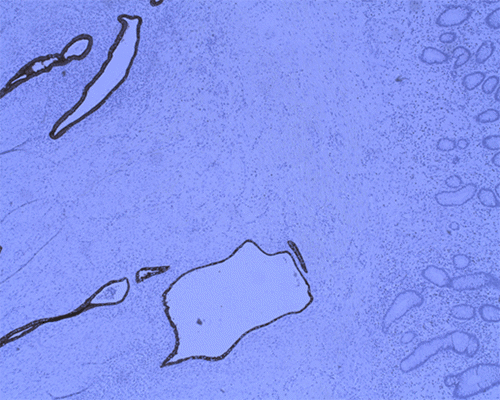

She underwent an EGD and colonoscopy, which was notable for a 30 mm polypoid appearing lesion coming from the appendiceal orifice (Figure 1) and an otherwise normal colon. Biopsies of the lesion showed fragments of colonic mucosa with hyperplastic change, fibrosis, crypt architecture distortion, and focal mild acute and chronic inflammation. A CT showed a tubular structure within the cecum measuring approximately 5 cm in length and 1 cm in width, concerning for an inverted appendix (Figure 2).

Figure 1. Colonoscopy Image of Inverted Appendix. Published with Permission

She underwent diagnostic laparoscopy. In the operating room, the appendix and the mesoappendix appeared to be partially intussuscepting into the cecum (Figure 3). It could not be reduced. There were no other abnormalities throughout her abdomen. A laparoscopic appendectomy and partial cecectomy were then performed (Figure 4). The specimen was taken en bloc without needing anastomosis (Figure 5). The frozen section in the operating room was negative for malignancy. Histopathologic evaluation of the specimen revealed an inverted appendix with endometriosis, surface erosion, serrated change, and reactive nuclear atypia. Sections demonstrated endometrial-type glands and stroma involving the appendiceal wall. Positive staining for ER, CK7, and PAX8 supports the diagnosis of an inverted appendix with endometriosis (Figure 6). It was negative for malignancy.

Figure 6. Immunostaining Profile, Demonstrating Endometriosis: A) CK7; B) ER, and C) PAX8. Published with Permission

A) Immunostaining Profile, Demonstrating Endometriosis: CK7

B) Immunostaining Profile, Demonstrating Endometriosis: ER

C)  Immunostaining Profile, Demonstrating Endometriosis:  PAX8